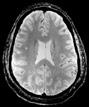

b) a) c) The Tic-Tac-Toe (TTT) radiofrequency head coil for 7T MRI Fig 1: in a), the implemented 16-channel TTT transmit RF coil; in b), the computational RF coil in c), the implemented RF coil with an 32-channel receive insert Fig. 2: The B1+ (magnetic field responsible for spin excitation) field homogeneity is highly degraded at 7T MRI due to a higher operational frequency (~297MHz). The TTT presents a more homogeneous field distribution when compared with the NOVA coil (a commercial coil) [1]. Measured Tic-Tac-Toe Measured Nova coil Regions with low B Simulated Tic-Tac-Toe B + maps in the brain: TTT vs NOVA RF coils TTT coil NOVA coil TTT coil NOVA coil Image comparison with the 32-channel NOVA commercial RF coil a) b) Fig. 3: In a), Turbo spin echo (TSE) sequence using the TTT coil with resolution of 0.4x0.4x2mm. In b), the same TSE sequence acquired with the commercial NOVA coil. In c), FLAIR sequence acquired with TTT coil with resolution of 0.7x0.7x2mm. In d), the same FLAIR sequence acquired with NOVA coil. The arrows point to regions of dark spots in the NOVA coil images and compare with similar regions on the TTT coil images [1]. c) d) High-resolution susceptibility weighted images showing cortical microvessels Fig 4 SWI images acquired at 0 2x0 2x1 5mm resolution In a) an axial slice of the whole brain image acquisition In b) and c), zoomed versions of a), detailing the micro-structures a) b) c) High resolution angiography without contrast agents 380μm a) b) Fig 5: Maximum intensity projection orientation and small vessels detectability isotropic image showing whole brain isotropic acquisition In d), 0 20mm are only detectable at higher resolution

Finger tapping task: activation of Functional MRI a) Diffusion MRI and fiber tracking Post-mortem a) a) b) Fig 7 In a), an structural MPRAGE image acquired at 0 75mm isotropic (skull removed using FSL package) In b), fiber tracking based on DTI acquisition, 64 directions, 1 5mm isotropic resolution The colors are defined for different orientations of the fibers Fig 8: In a), susceptibility weighted images acquired at 0 35mm isotropic, 32 min acquisition time, in a post-mortem brain fixated with formalin In b), a photograph of similar slice in the same brain Table 1: 7T MRI studies conducted at the RF Research Facility at University of Pittsburgh White matter legions (circle): Multiple Sclerosis study Stroke (circle): sickle cell disease study Automatic hippocampus segmentation: Midlife Neurocognitive Lacunar infarct (arrow): depression study White matter hyperintensities (arrows): Healthy Brain aging study (left) and Small Vessels disease in preclinical Alzheimer’s disease study (right) Fig 9: Sample of some studies listed in Table 1 using the developed 16 array (Fig a) There are 4 completed studies and 13 ongoing patient studies with approximated 2 000 patients scheduled FUTURE DIRECTIONS 64-channel Tic-Tac-Toe RF transmit coil for 7T MRI 0 Fig 10: In a), the 64-channel transmit coil computational modeling [2] To improve the field of view of the projector/monitor in fMRI studies, the frontal panels can be removed, resulting in a 56-channel coil In b), one assembled side of the coil In c), simulated B1+ field distribution: for an 8kW power amplifier capabilities (default in older 7T MRI scanners) a homogeneity (measured by the coefficient of variationCV) of 15 2% is achieved in the brain For an 16 kW power amplifier (available for the recently FDA approved Siemens 7T MAGNETOM Terra), an CV of 10 6% can be achieved in the brain 16 kW power amplifier: 8 kW power amplifier: a) b) c) max